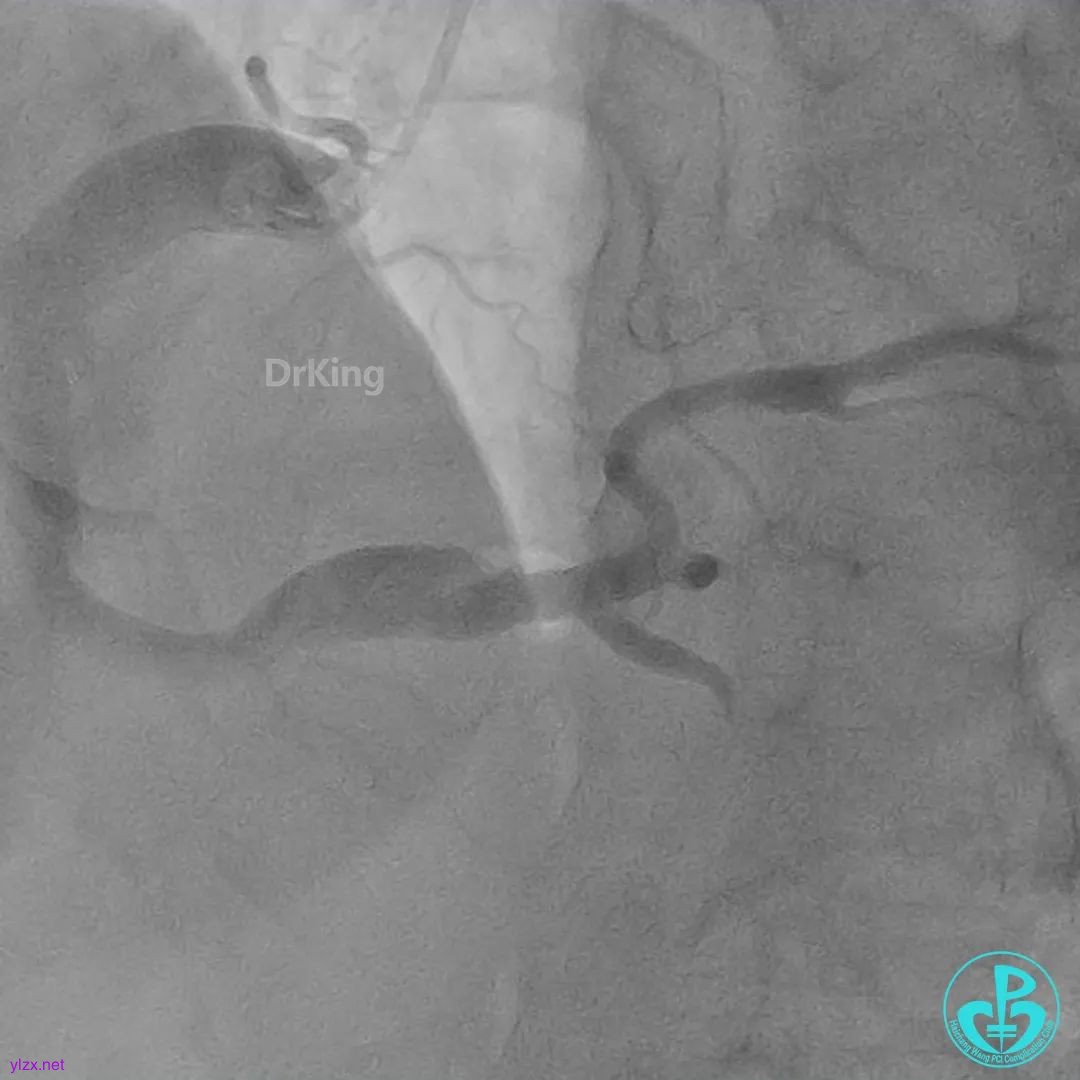

06 8天后复查冠脉造影

RCA粗大近中段瘤样扩张明显,中段血栓影消失,左室后支显影,后降支近段可见造影剂滞留, TIMI血流3-级。

RCA粗大全程瘤样扩张明显,自近段闭塞,TIMI血流0级;可见自身桥侧支逆供RCA远段。

LM未见明显狭窄,LAD开口至近段明显瘤样扩张,自近段闭塞,TIMI血流0级,D1瘤样扩张,TIMI血流2级;可见D1逆供LAD中远段及RCA中远段。

LCX发育小,内膜不光滑,TIMI血流3-级,逆供RCA中远段。